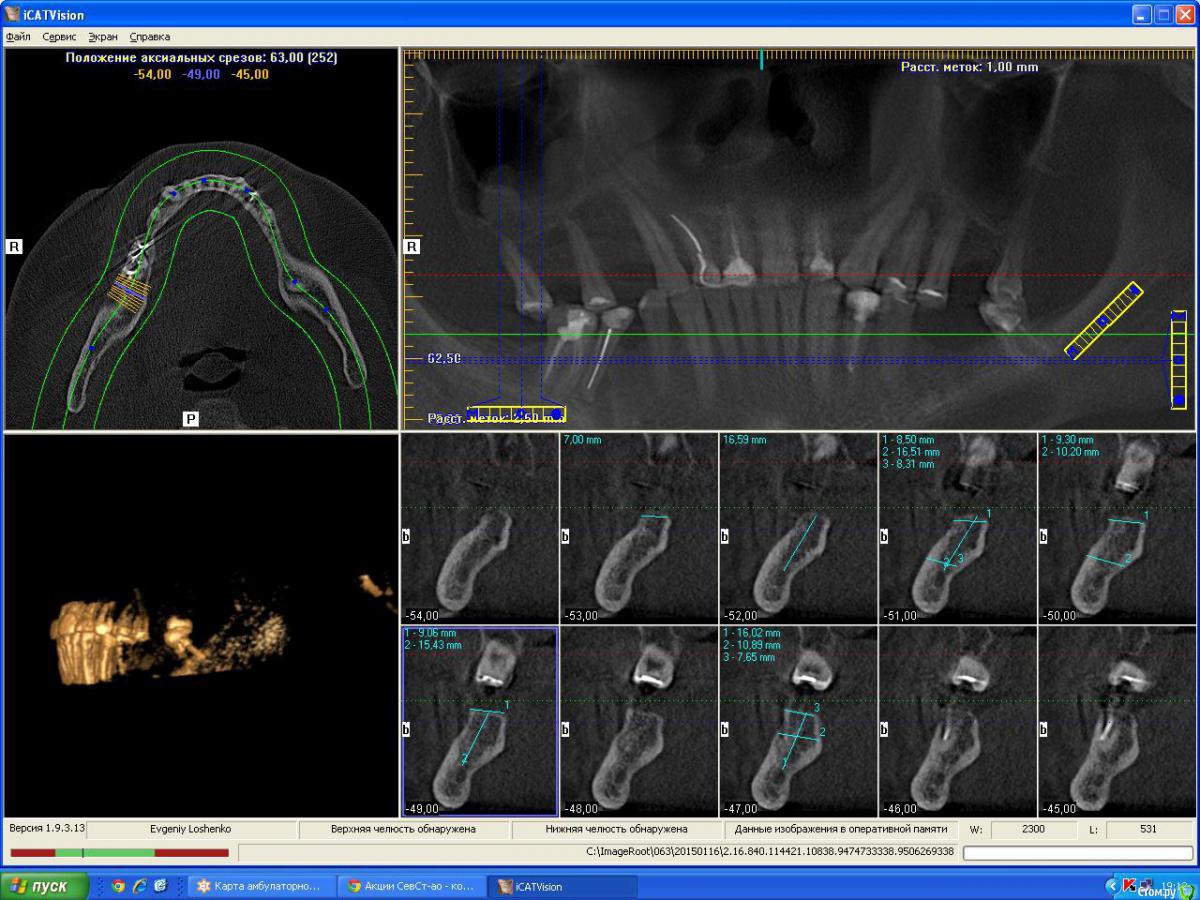

denis1987 Опубликовано 25 февраля, 2015 Поделиться Опубликовано 25 февраля, 2015 Вот такой вот пациент , с адентией в 1 , 2 , 3 и 4 сегментам. Фото прилагаются. Ссылка на комментарий

denis1987 Опубликовано 25 февраля, 2015 Автор Поделиться Опубликовано 25 февраля, 2015 Вот ничего другого на ум не приходит как аугментация костными блоками аутогенными, по крайней мере в 1 и 3 сегментах. Во 2м егменте расщепление + закрытый синус, в 4м вроде как хороший аэродром. Интересует мнение форумчан. Ссылка на комментарий

Aquarius Опубликовано 25 февраля, 2015 Поделиться Опубликовано 25 февраля, 2015 (изменено) Ну в области 14-го ламина точно сработает. И Вы планируете аугментацию на неправильно выставленных срезах!!! Изменено 25 февраля, 2015 пользователем Aquarius Ссылка на комментарий

denis1987 Опубликовано 25 февраля, 2015 Автор Поделиться Опубликовано 25 февраля, 2015 Почему вы думаете что срезы неправильно выставлены ? Ссылка на комментарий

Aquarius Опубликовано 25 февраля, 2015 Поделиться Опубликовано 25 февраля, 2015 область 26. Срез не захватывает полностью гребень. Не знаю,может я ошибаюсь. Ссылка на комментарий

denis1987 Опубликовано 25 февраля, 2015 Автор Поделиться Опубликовано 25 февраля, 2015 Денис,когда планируете аугментацию? Если не в ближайшие несколько дней, то я постараюсь выложить отпротоколированный кейс с ламиной в области 14. Может что-то возьмете на вооружение. Вроде наконец учёл все ошибки)) И что-то выросло.Все , я понял про что вы говорили в плане среза , на самом деле кусок альвеоляра не влез , настроил норм , но все равно картина не сильно изменилась к сожалению ( Ссылка на комментарий